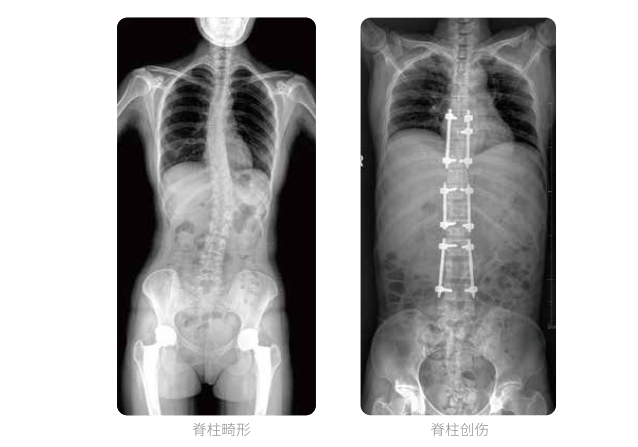

全脊柱臨床影像

普愛(ài)醫(yī)療動(dòng)態(tài)數(shù)字化X線攝影(動(dòng)態(tài)DR)可以使整個(gè)脊柱一次成像,直觀顯示脊柱的整體形態(tài)以及側(cè)彎部位,評(píng)價(jià)側(cè)彎的病理程度,全面了解脊柱各個(gè)階段的生理曲度及椎間關(guān)節(jié)連接的關(guān)系,避免了常規(guī)脊柱攝影對(duì)整個(gè)脊柱曲度的影響。為脊柱側(cè)彎的診斷治療提供了重要的影像學(xué)依據(jù)。